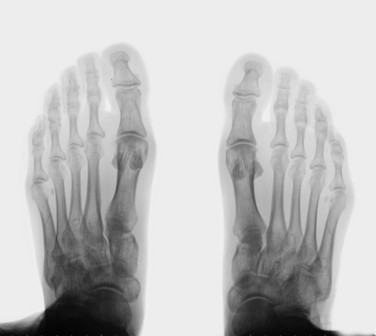

La exploración clínica y las pruebas de imagen son fundamentales para poder establecer el diagnóstico diferencial. Las radiografías en carga son esenciales como primera prueba y cuando junto con la exploración clínica se sospeche que exista una causa mixta o una complicación será la ecografía y la resonancia magnética las exploraciones complementarias necesarias.